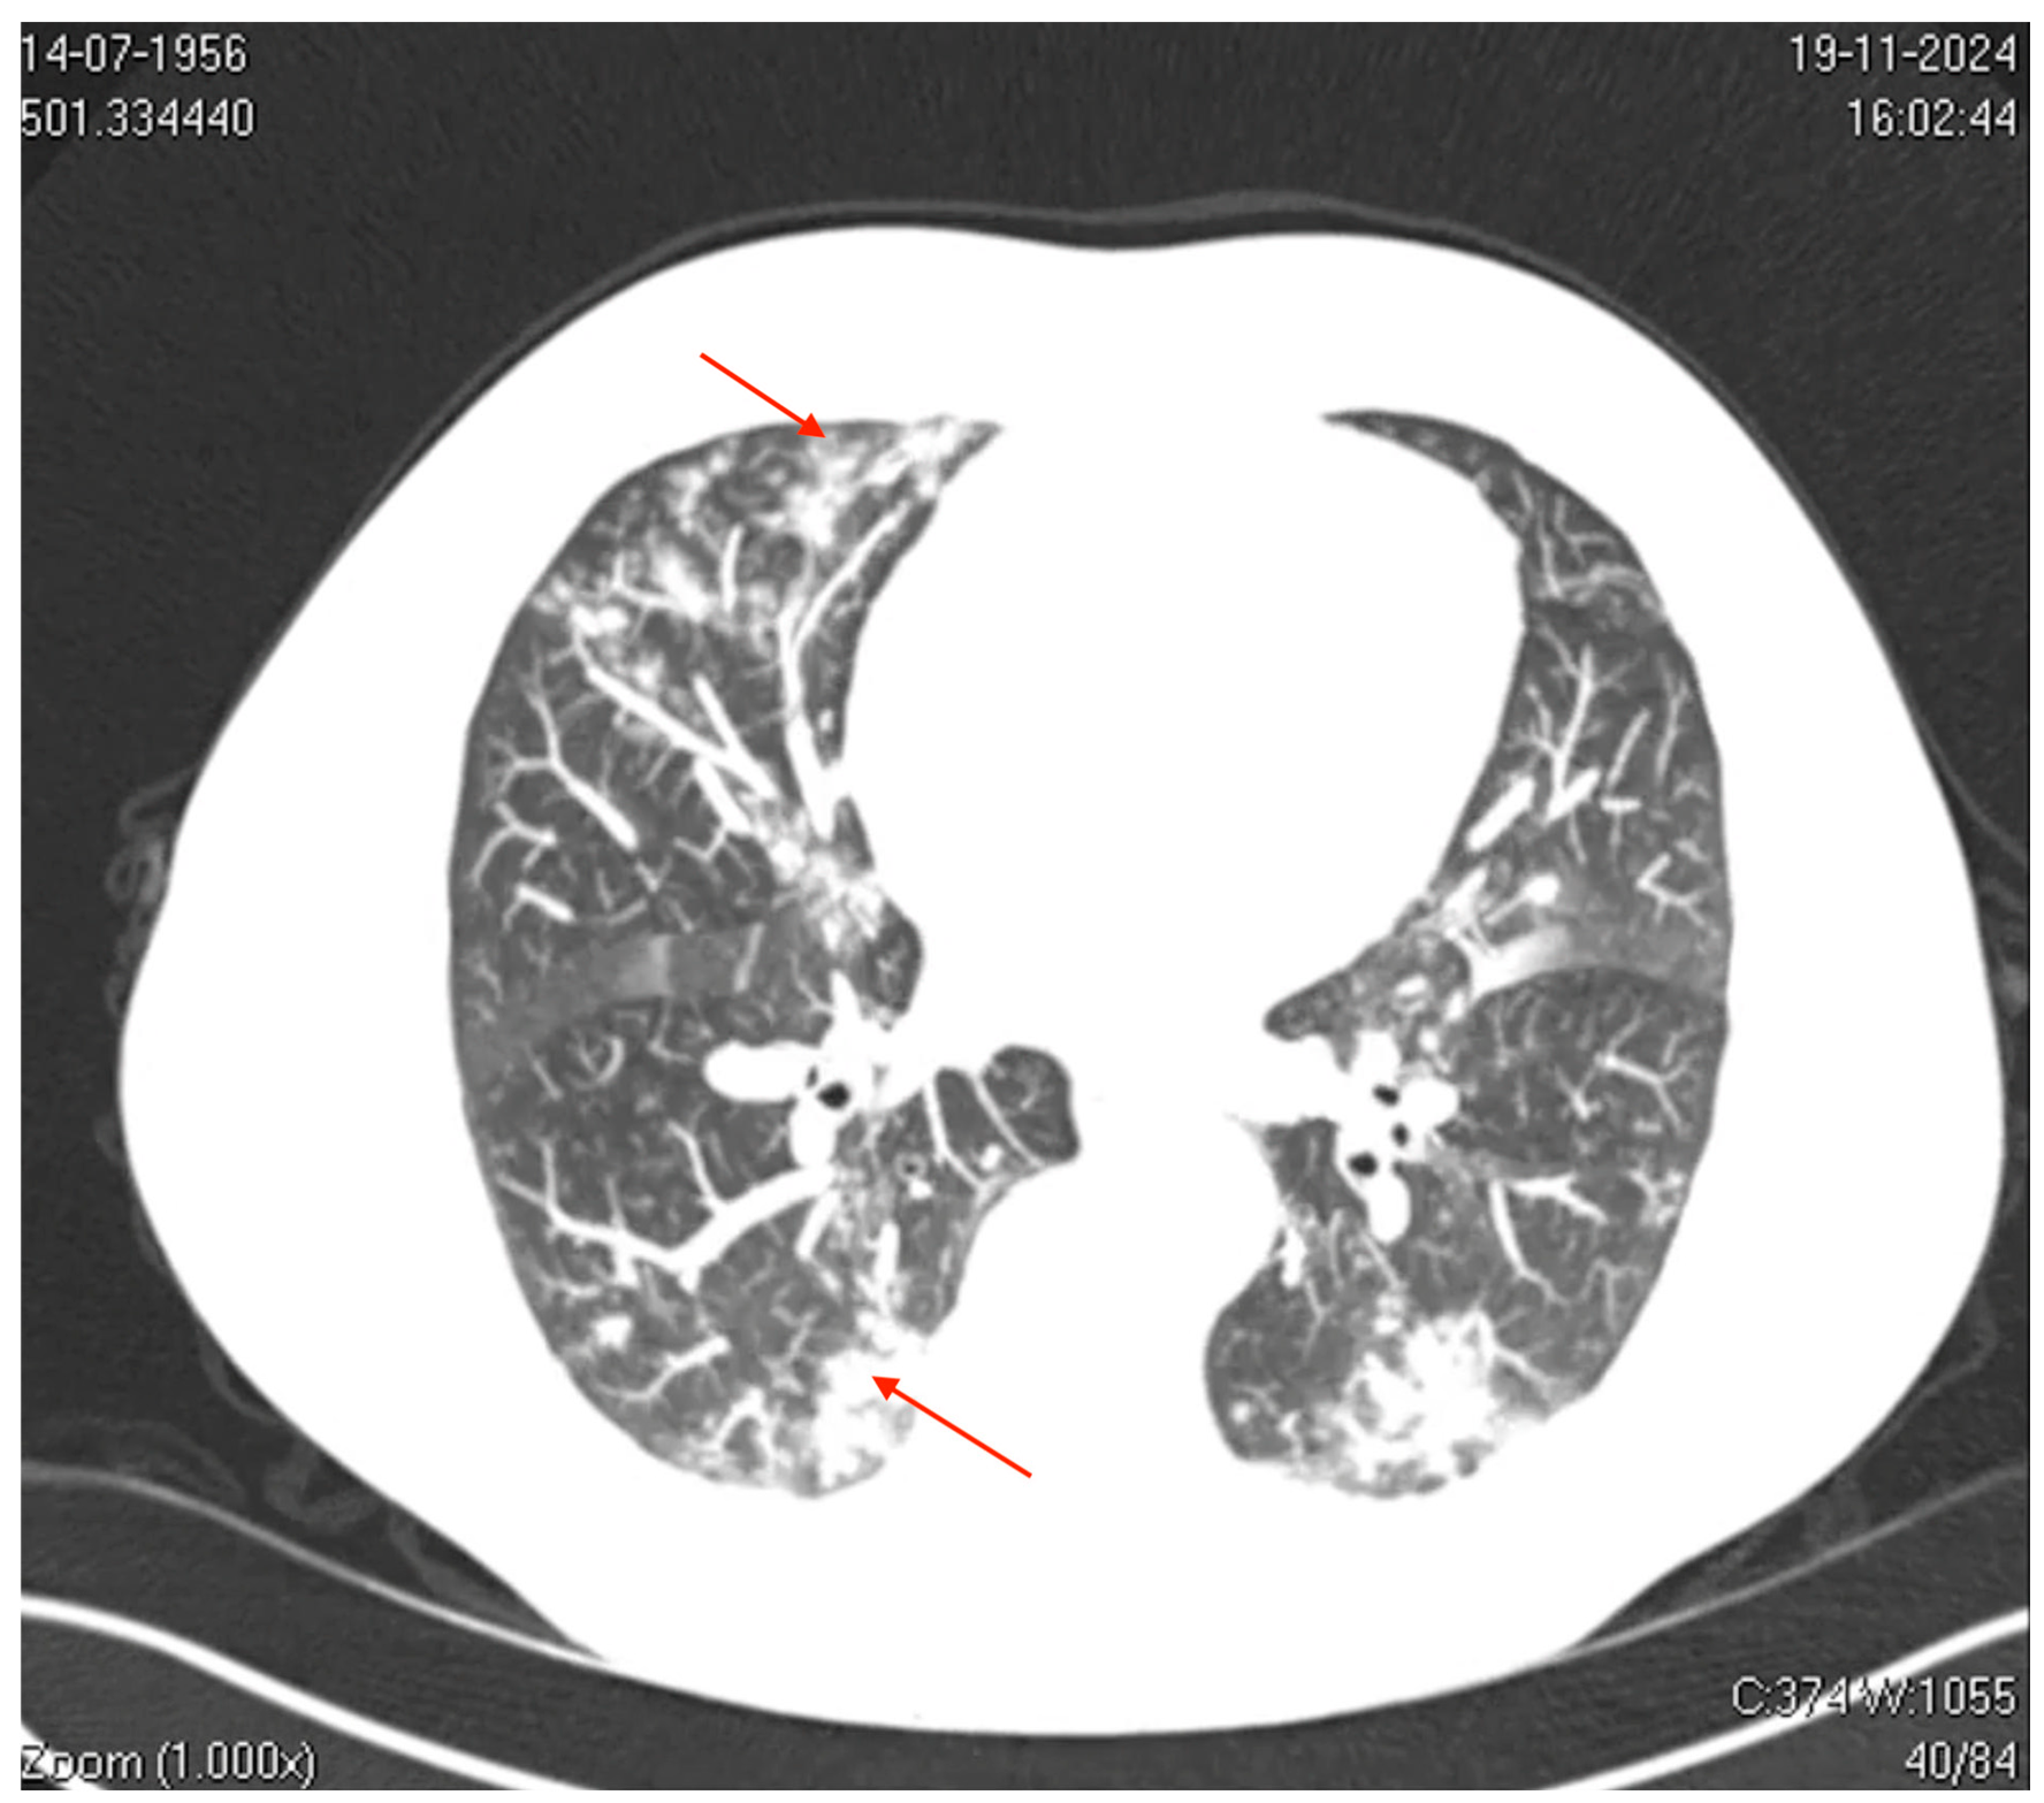

On (D7), he was admitted to the Emergency Department with SpO2 levels of 91–92% on room air, tachypnea, fatigue, an axillary temperature of 37.8 °C, and blood pressure of 140/80 mmHg. (Figure 1). Laboratory findings included elevated inflammatory markers (C-reactive protein, 7.6 mg/dL; D-dimer, 870 ng/mL), mild transaminase elevation, and thrombocytopenia, while leukocyte counts and procalcitonin levels remained normal, suggesting a viral etiology. Imaging studies revealed significant pulmonary involvement (Figure 2).

Axial computed tomography (CT) of the thorax revealed mild bilateral pleural effusions, small centrilobular opacities with multilobar distribution, and ground-glass opacities, some of which were coalescent and interspersed with areas of consolidation. These findings predominantly affected the left upper and lower lobes, involving the pulmonary interstitium and peripheral airways (acinus and bronchioles), which is consistent with a viral pneumonia pattern.

3.2.2. Clinical-Radiological Correlation

The radiological findings, characterized by diffuse ground-glass opacities and consolidations predominantly in the lower lobes, are consistent with the typical imaging pattern observed in viral pneumonia [21]. These radiological features overlap with those observed in other viral infections, such as SARS-CoV-2 and RSV, complicating diagnostic differentiation. However, the absence of bacterial consolidation patterns and low procalcitonin levels substantiated a viral etiology without bacterial superinfection [2]. This case highlights the importance of integrating radiological, clinical, and molecular data for accurate diagnostic assessment during seasonal respiratory surges.

Figure 2. Axial computed tomography (CT) image of the thorax. The image shows bilateral ground-glass opacities with a reticular pattern interspersed with focal areas of consolidation and peripheral bronchiolar filling. The red arrows highlight specific areas of consolidation surrounded by ground-glass opacities, which are more prominent in the peripheral and lower lung regions. These findings suggest a diffuse inflammatory or infectious process involving the pulmonary interstitial and peripheral airways (acinus and bronchioles), which is consistent with viral pneumonia.